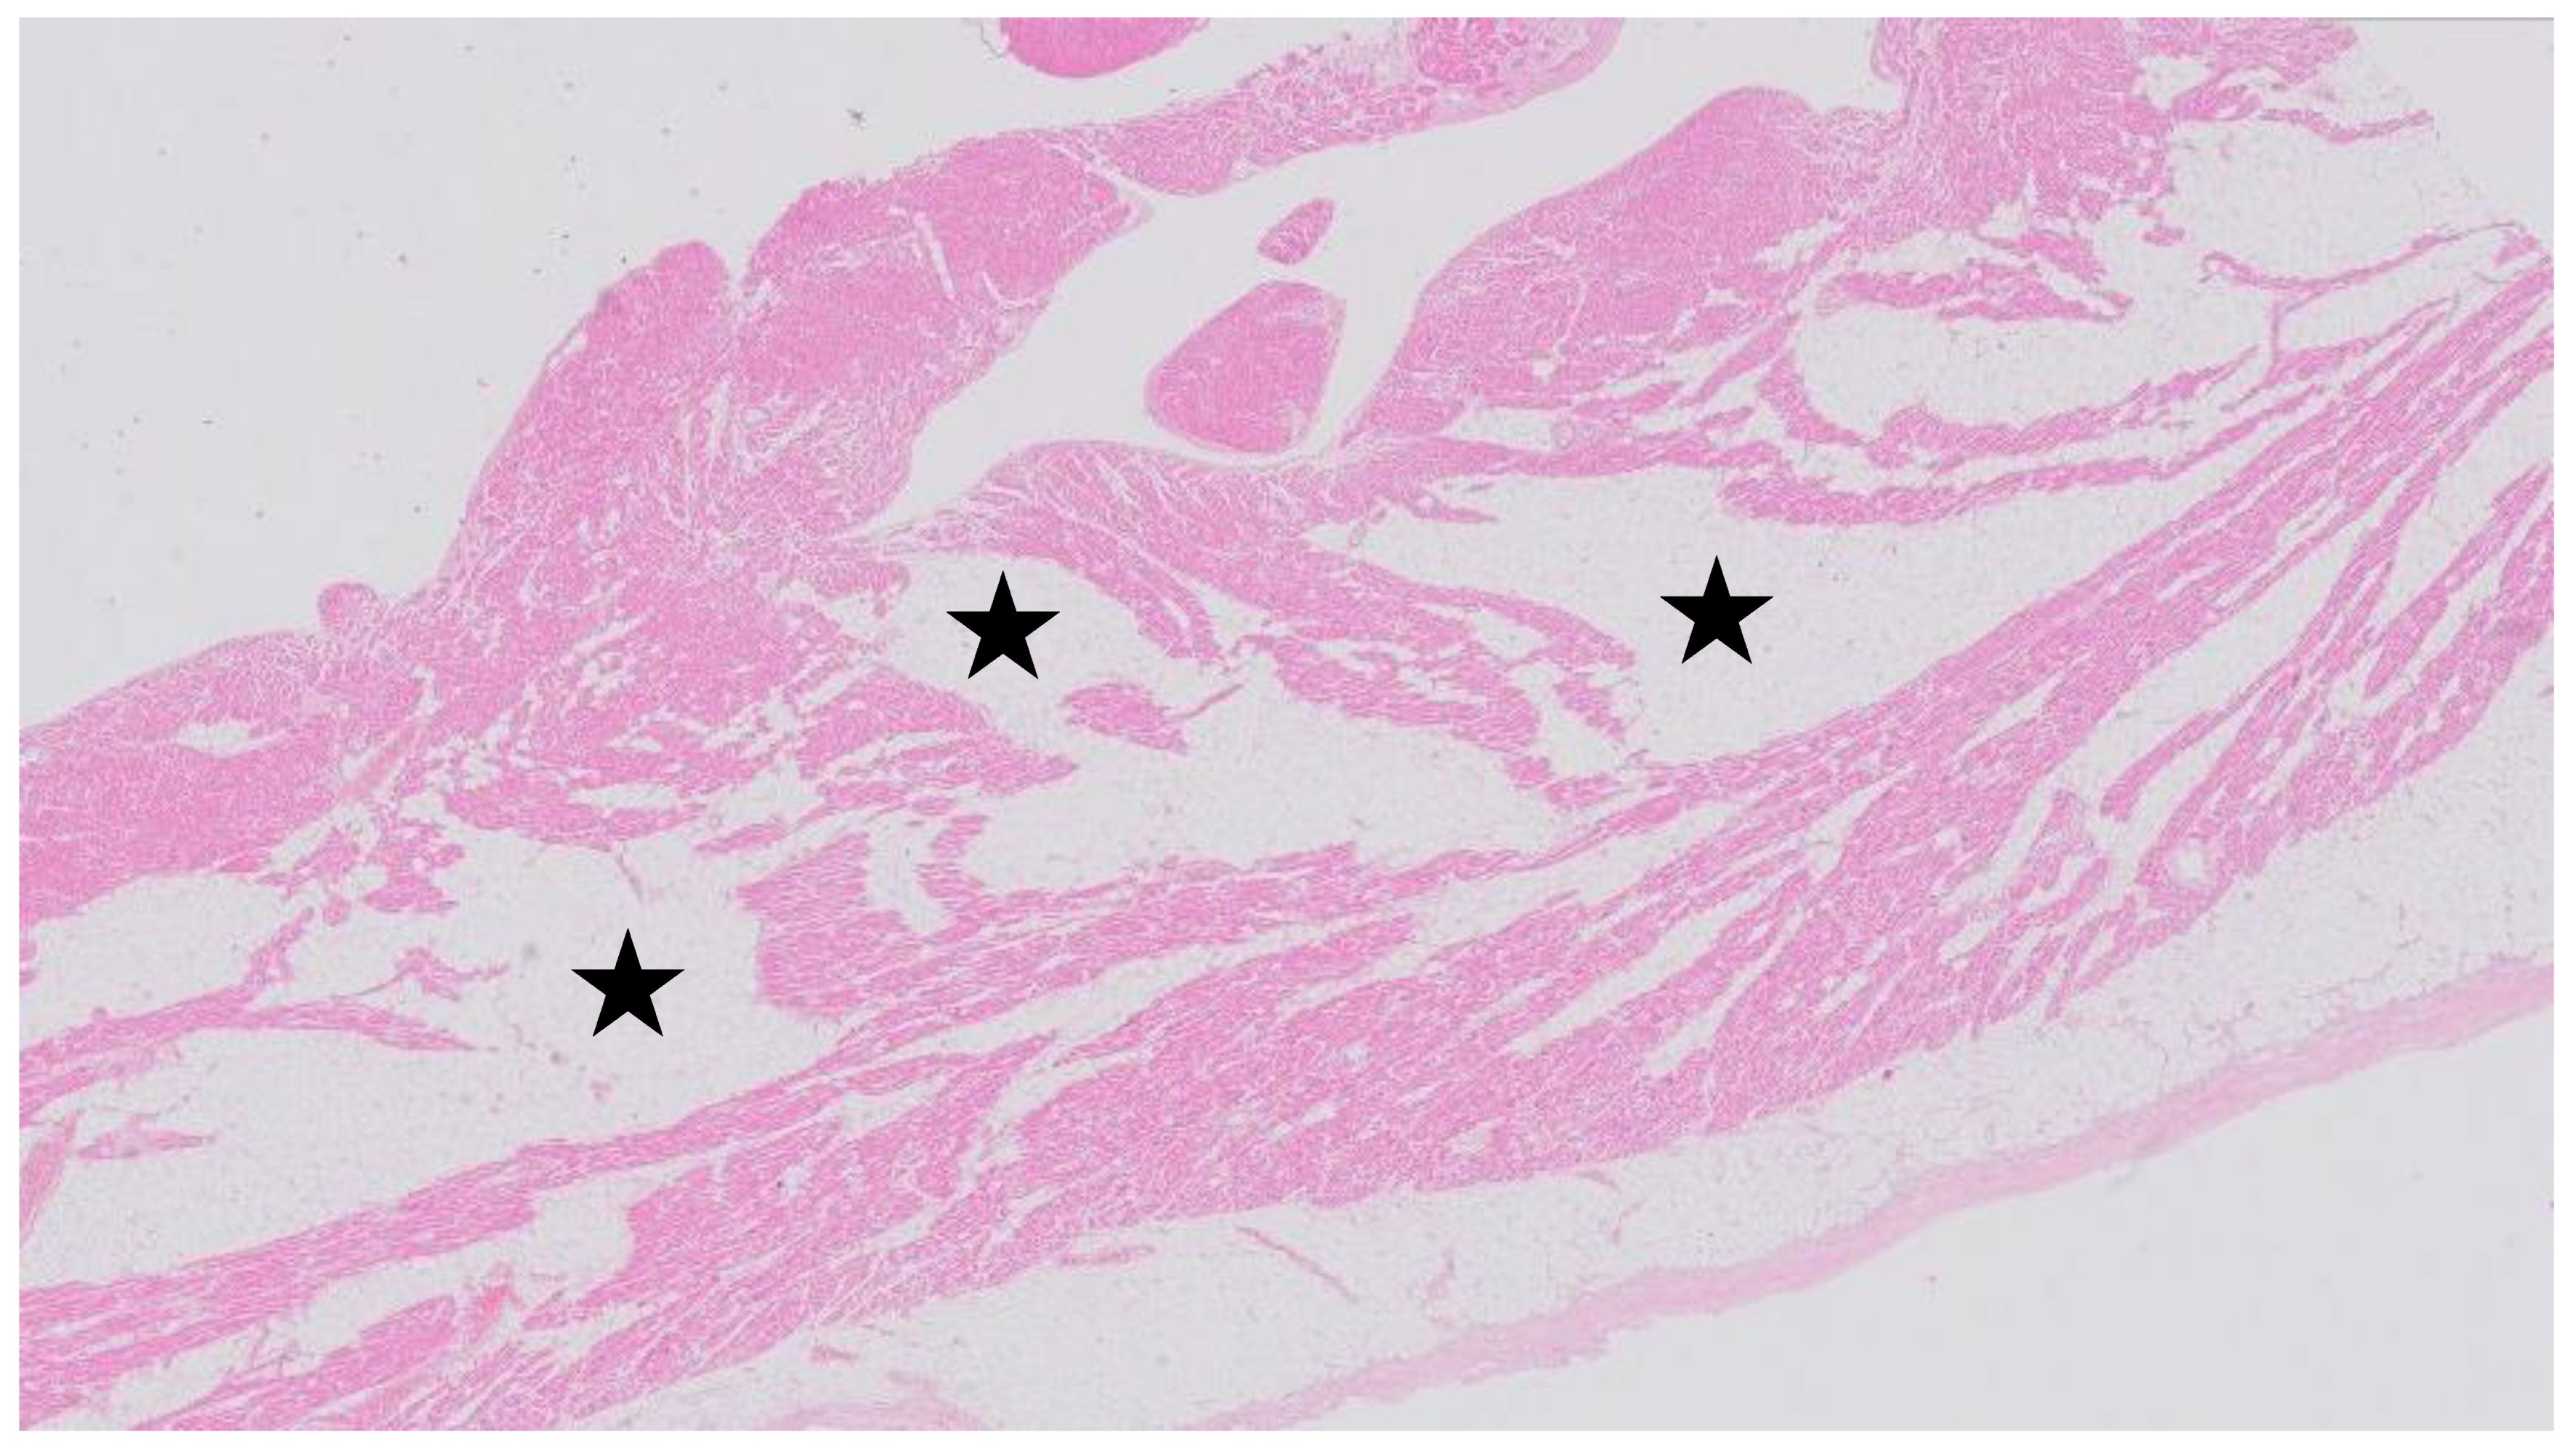

Case 1. An autopsy was performed on a 60-year-old woman that died due to progressive bilateral pulmonary vein thrombosis of unknown cause. Her cardiovascular history was negative for syncope or palpitations. Family history was negative for sudden cardiac death. Extensive bilateral pulmonary vein thrombosis was confirmed on autopsy. In addition, in the right ventricle of the heart extensive fatty changes of the myocardium were observed, partly subendocardial with minor fibrosis (Figure 1).

Figure 1.

Hematoxylin- and Eosin-stained section of the right ventricle of the heart with extensive fatty changes of the myocardium, partly subendocardial, with only minor fibrosis. Asterisk indicates fatty tissue.